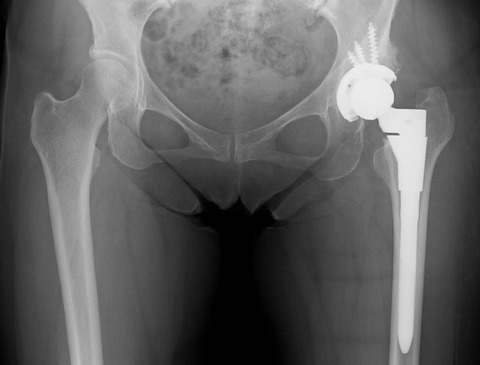

かなり検討したのですが、結局カップの前方開角度は通常の症例と同様に20度に減捻して、腸腰筋の Irritationにはある程度目をつぶることしました。

大腿骨にも過大前捻があり、関節不安定性がどうなるのか予測できなかったため、S-ROM-Aでこちらも20度減捻しました。

寛骨臼、大腿骨頚部とも大幅に角度調整したのですが、幸いにも易脱臼性はありませんでした。こういう症例は疲れますね...。